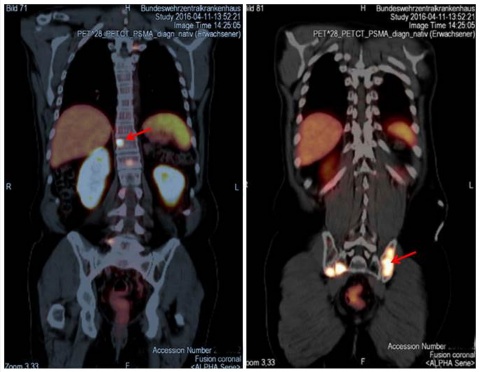

Seit Einführung der Substanz und Methode hat eine umfangreiche Zahl von Publikationen deren klinischen Wert bestätigt. So berichteten GIESEL et al. [13] in ihrer Studie, in der sie die PSMA PET/CT mit der konventionellen morphologischen Bildgebung mit CT bei Patienten vor Beginn einer Strahlentherapie untersuchten, dass mit den morphologischen Kriterien der CT, die im Wesentlichen auf Größe und Form der Lymphknoten basiert, nur 22 % der PSMA-positiven Läsionen als verdächtig für ein malignes Geschehen klassifiziert wurden. Bei zwei Drittel der Patienten erfolgte im Vergleich zwischen PSMA PET/CT und 3-D-volumetrischer CT ein „Upstaging“ von cN0 auf cN1. Vorhergehende Studien hatten gezeigt, dass diesbezüglich ein hohes Signal-zu-Hintergrund-Verhältnis typisch für die PSMA PET/CT ist [2, 4, 25]. In der gleichen Studie [13] wurde demonstriert, dass die kleinste PET-positive Läsion (in diesem Fall ein Lymphknoten) einen Kurzachsendurchmesser von nur 2,4 mm hatte. Dies bedeutet, dass man hier fast an die Grenze der physikalisch bedingten Erreichbarkeit (1,7 mm) des Verfahrens gelangt ist. Gerade beim Setting für Patienten, die für eine Salvage-Strahlentherapie vorgesehen sind, wurde der hohe Wert der PSMA PET/CT erkannt. Empfohlen wird dabei, die Salvage-Strahlentherapie am besten bei PSA-Leveln < 0,5 ng/ml durchzuführen [16, 27]. Es wurde gezeigt, dass selbst bei solch niedrigen Leveln von PSA die PSMA PET/CT in der Lage ist, pathologische Anreicherungen außerhalb der Prostata-Loge zu entdecken. Häufigste Lokalisation waren hierbei die Beckenlymphknoten in ungefähr der Hälfte der Patienten mit einem positiven PET/CT-Scan (Abbildung 2). Dies würde bedeuten, dass bei etwa einem Viertel aller Patienten, die mit solch niedrigen PSA-Leveln der PSMA PET/CT zugewiesen werden, eine Änderung im Behandlungsplan erfolgt [1, 11]. Das bedeutet, dass die PSMA PET/CT die Behandlungsabläufe beeinflussen wird, z. B. im Sinne der Vermeidung einer nicht effektiven Strahlentherapie mit nicht zu vernachlässigenden Nebenwirkungen oder etwa auch einer strahlentherapeutischen Behandlung mit Inklusion der affektierten Lymphknoten in das Strahlenfeld. Aktuelle Untersuchungen konnten auch zeigen, dass die exzellente Bildqualität, die höhere Spezifität und die gute Korrelation der PSMA-Aufnahme mit dem Gleason Score die PSMA PET der Cholin PET überlegen machen [17, 20].

In der Abteilung Nuklearmedizin des BwZKrhs Koblenz wurden seit Juli 2015 insgesamt 193 Untersuchungen mit der PSMA PET/CT durchgeführt. Wir hatten die Gelegenheit in einer ersten Serie von Patienten nach Etablierung der PET/MRT im BwZKrhs Koblenz 34 Patienten, die eine PET/CT erhalten hatten, unmittelbar im Anschluss an diese einer PET/MRT-Untersuchung zuführen zu können (Abbildung 3).